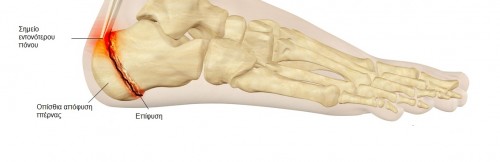

Στους ενήλικες και τα ηλικιωμένα άτομα παρατηρείται η πελματιαία απονευρωσίτιδα κατά την οποία υπάρχει πόνος στην έκφυση της πελματιαίας απονεύρωσης από την πτέρνα, ο πόνος αυτός είναι εντονότερος κατά την έγερση από το κρεβάτι μετά τον ύπνο και γίνεται ηπιότερος μετά τα πρώτα βήματα .Εντοπίζεται συνήθως στην κάτω και έσω πλευρά της πτέρνας.

Πελματιαία απονευρωσίτιδα

Θεραπεία : Αρχικά η θεραπεία ξεκινάει με ποιό συντηρητικά μέσα όπως αντιφλεγμονώδη φάρμακα φυσικοθεραπείες διάτασης της πελματιαίας απονεύρωσης και του γαστροκνήμιου μυός , παγοθεραπεία και χρήση μαλακών επιθεμάτων σιλικόνης .

Επί επιμονής της συμπτωματολογίας καταφεύγουμε σε ενέσεις κορτιζόνης και κρουστικό υπέρηχο (ESWT) και τέλος σε χειρουργική αντιμετώπιση.

Μερικές φορές κατά τον ακτινολογικό έλεγχο μπορεί να διαπιστωθεί άκανθα της πτέρνας στην έκφυση της πελματιαίας απονεύρωσης, η οποία όμως δε φαίνεται να είναι η αιτία του πόνου, γι” αυτό και σπάνια χρειάζεται η χειρουργική αφαίρεση της.

Πτερνική άκανθα